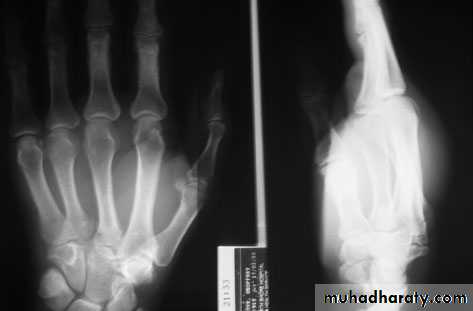

FAILURE OF FORMATION

Transverse arrest:The most common levels of absence are at the proximal forearm and midcarpus, then at the metacarpals and humerus.

Transverse arrest of fingers

microvascular transfer of a toe

non-vascularized transfer of a toe phalanx

Longitudinal arrest

radial (pre-axial),ulnar (post-axial),

central (cleft hand) or

intersegmental (intercalated) structures

RADIAL DYSPLASIA

rare condition (incidence 1:50 000 to 1:100 000 live births)may involve any (or all) of the structures from the elbow to the thumb, it usually occurs as an isolated abnormality

occasionally associated with other skeletal, cardiac, haematological, renal or craniofacial anomalies

The infant is born with the wrist in marked radial deviation ‘radial club hand’

half the patients are affected bilaterally

There is absence of the whole or part of the radius; often the thumb, scaphoid and trapezium fail to develop normally.